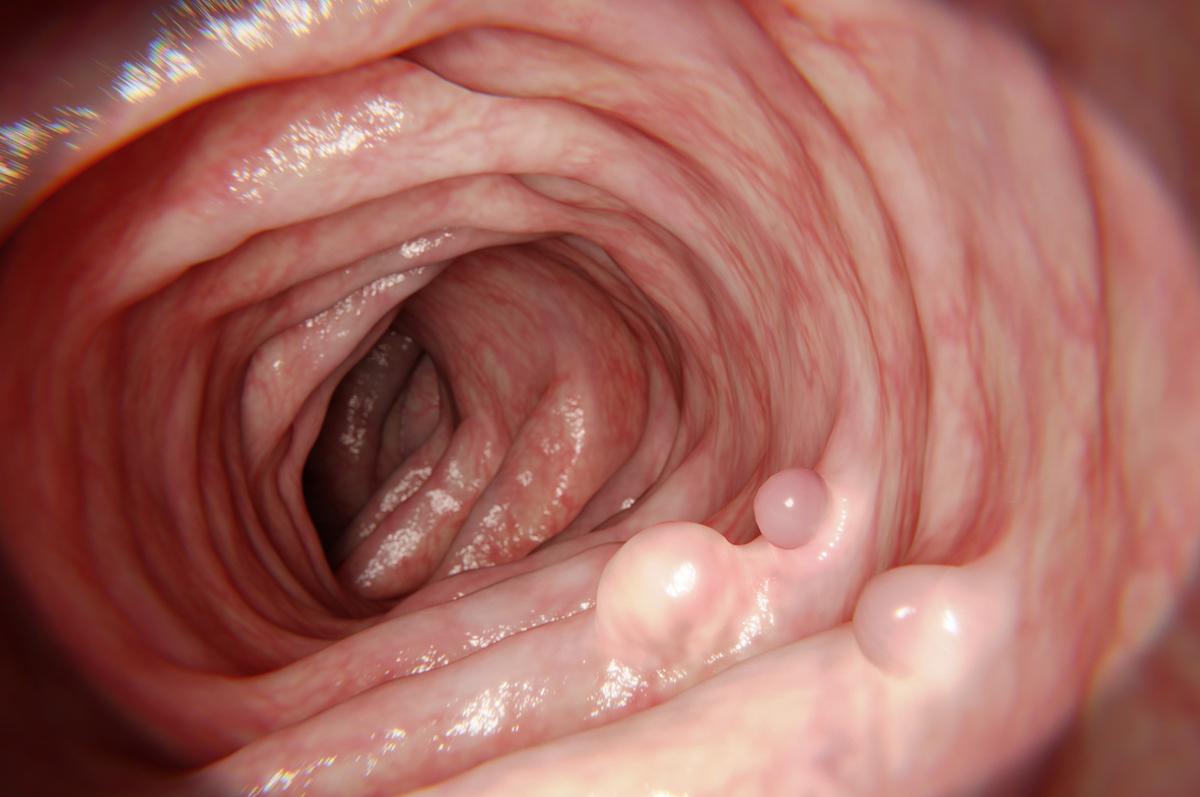

Le traitement de la douleur chronique nécessite une approche multidisciplinaire, combinant des traitements médicaux, des thérapies physiques et, dans certains cas, des interventions psychologiques. Les AINS peuvent encore jouer un rôle dans la gestion de la douleur chronique, mais leur utilisation prolongée doit être surveillée pour éviter les effets secondaires à long terme, comme les troubles gastro-intestinaux.